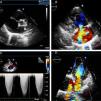

Her situation was reassessed after an episode of atypical chest pain and palpitations with negative ischemia testing. The echocardiogram revealed moderate right ventricular (RV) dilatation with severe hypertrophy and preserved systolic function, a large ostium secundum ASD with predominantly left-to-right bidirectional shunt (Figure 1A), severe tricuspid regurgitation (Figure 1B and C), and moderate mitral regurgitation (Figure 1D) with evidence of severe pulmonary hypertension and dilatation of the pulmonary trunk.